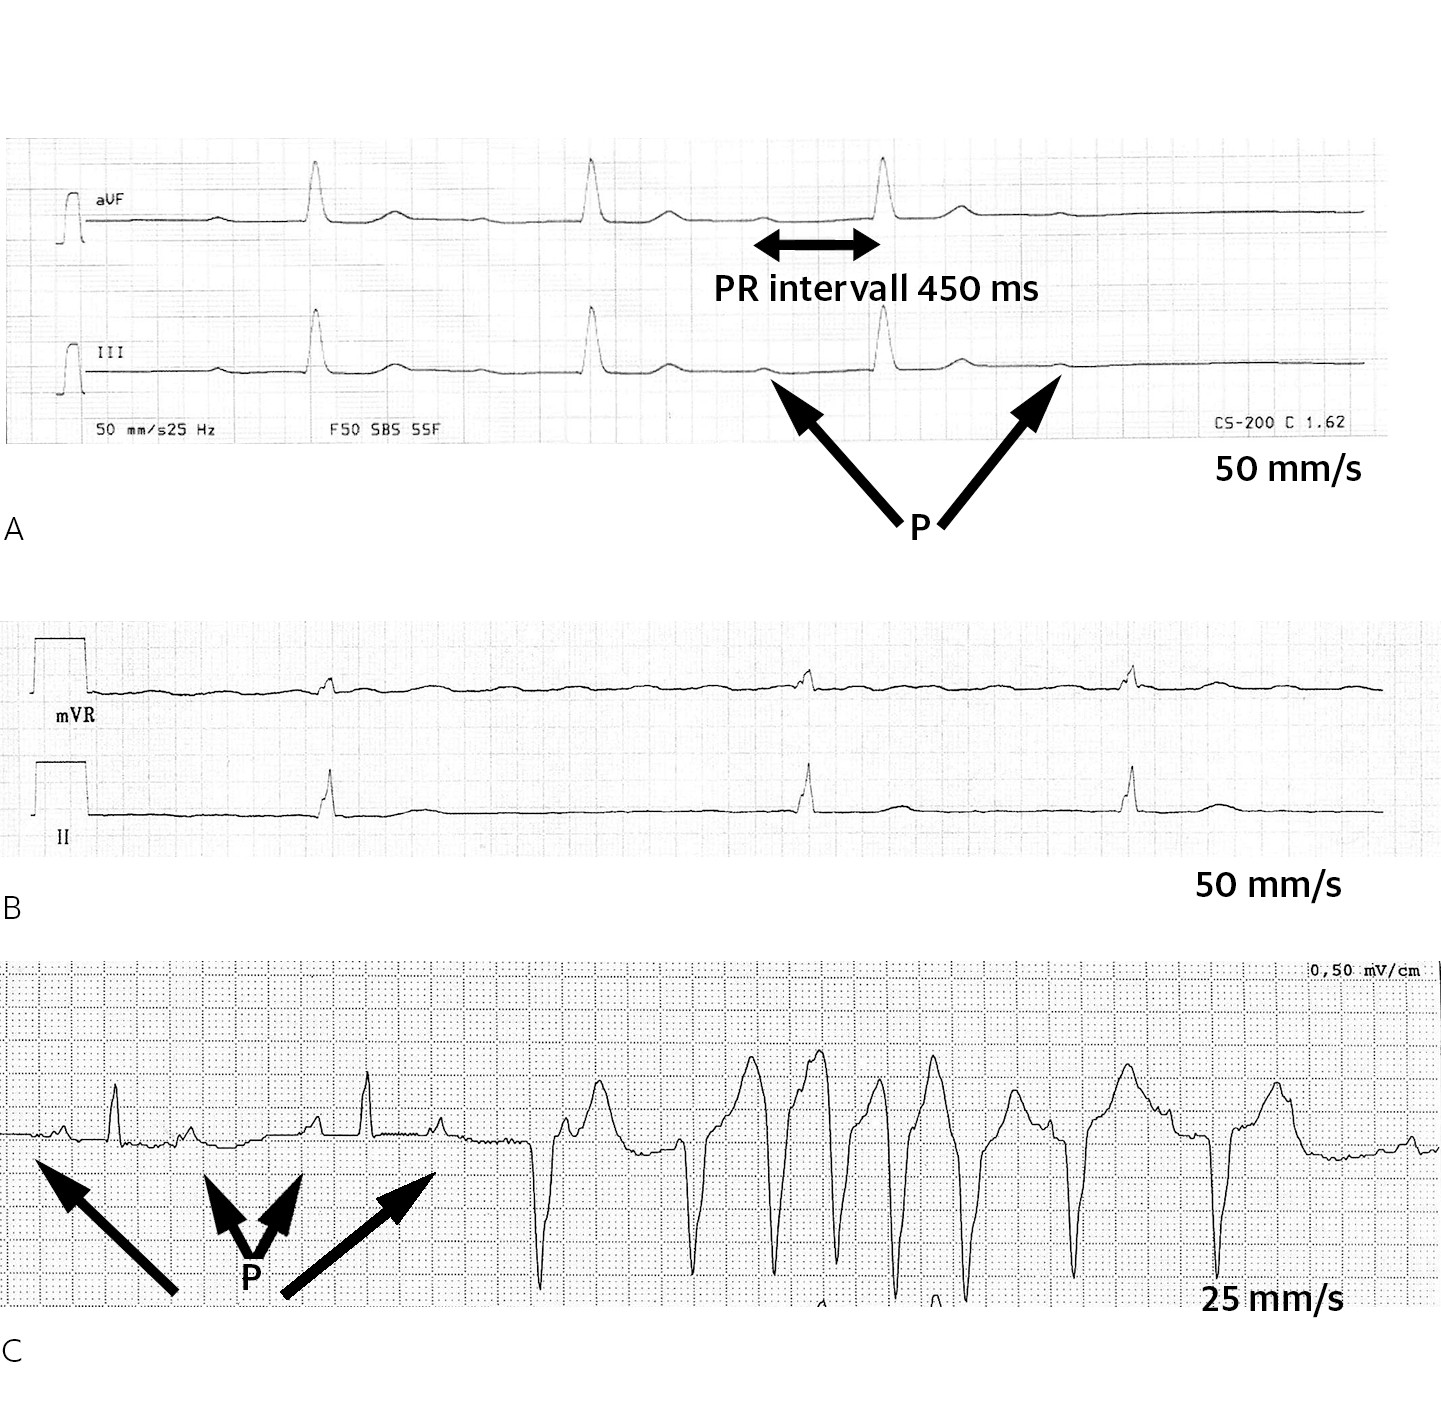

Den kardiale fenotypen ved de autosomalt dominante LMNA-mutasjonene har nær 100 % livstidspenetrans, som innebærer at nærmest alle mutasjonsbærere utvikler hjertesykdom i løpet av livet (13). Kardiomyopatien debuterer oftest med AV-blokk og/eller supraventrikulær arytmi (oftest atrieflimmer og atrieflutter) i ung voksenalder (fig 2). Progredierende AV-blokk medfører behov for pacemakerinnleggelse. Sviktende venstre ventrikkel-funksjon med utvikling av dilatert kardiomyopati kommer typisk senere i forløpet (12, 14). Helt sentralt for pasientbehandling og oppfølging er den særlig høye risikoen for livstruende ventrikulære arytmier og plutselig hjertedød som ikke sjelden oppstår før utvikling av manifest dilatert kardiomyopati. En skandinavisk tverrsnittsstudie viste at 51 % av pasientene hadde dokumentert ventrikulær arytmi (14), og i en metaanalyse ble det rapportert at LMNA-pasientene hadde fire ganger høyere insidens av plutselig hjertedød (46 % av dødsfallene) sammenlignet med død fra terminal hjertesvikt (12 % av dødsfallene) (15). Pasienter med LMNA-mutasjon må derfor følges hyppig allerede før påvisning av svekket myokardfunksjon. Nedsatt venstre ventrikkel-ejeksjonsfraksjon, mutasjoner som introduserer et stoppkodon, endrer RNA-spleising eller leserammen, samt maskulint kjønn og nedsatt New York Heart Association (NYHA)-funksjonsklasse er tidligere vist å være risikomarkører for ventrikkeltakykardi (4, 13). Videre er forlengelse av PR-intervallet (AV-blokk grad I), AV-blokk grad II-III, fibrose i septum ved kardial MR og dyssynkroni målt ved ekkokardiografisk deformasjonsanalyse (strain) funnet å være risikomarkører for ventrikkeltakykardi (14, 16).

Siden ventrikkeltakykardi er hyppig og AV-blokk er en risikomarkør for ventrikulær arytmi (14), anbefales det fra flere norske og internasjonale fagmiljøer å implantere en primærprofylaktisk hjertestarter direkte når pasienten har behov for pacemaker grunnet AV-blokk, uavhengig av ejeksjonsfraksjon (18). Det er etter hva vi kjenner til, ikke vist at tilstedeværelse eller fravær av muskeldystrofi er en risikomarkør for ventrikulær arytmi ved LMNA-mutasjon. Ofte debuterer pasienter med LMNA-mutasjon med kardiale symptomer før muskeldystrofi, og ikke alle utvikler muskelsymptomer i det hele tatt. Kombinasjonen av AV-blokk, atrieflimmer/atrieflutter og ventrikkeltakykardi (fig 2), særlig hos pasienter med hjertesykdom i familien, må få kardiologen til å tenke på LMNA-sykdom og, slik vi ser det, iverksette henvisning til gentesting for dette ved et senter med kompetanse på genetisk hjertesykdom. Ved Oslo universitetssykehus praktiseres gjensidig henvisning av LMNA-pasienter mellom kardiologisk og nevrologisk avdeling for å dekke hele fenotypen.